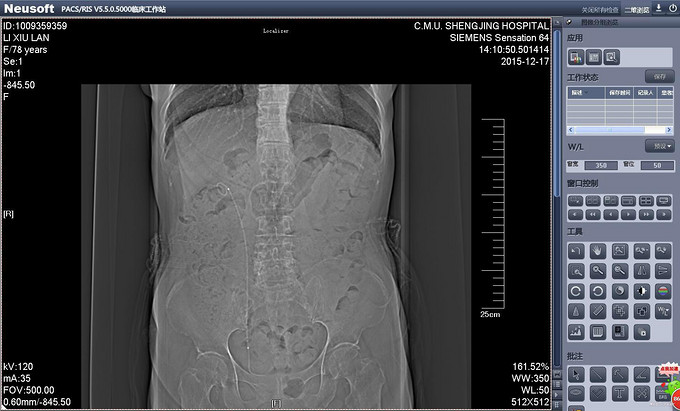

辅助检查:PCNL术后出院前复查CT提示双J管位置位于膀胱内。(图术后复查CT 1、2) 输尿管镜拔管前再次复查CT提示双J管缩回输尿管内(缩回后CT1、2)